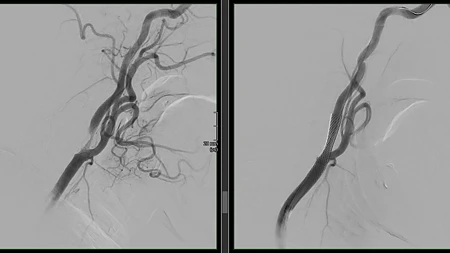

Zweitmeinung bei Karotisstenosen offiziell Kassenleistung